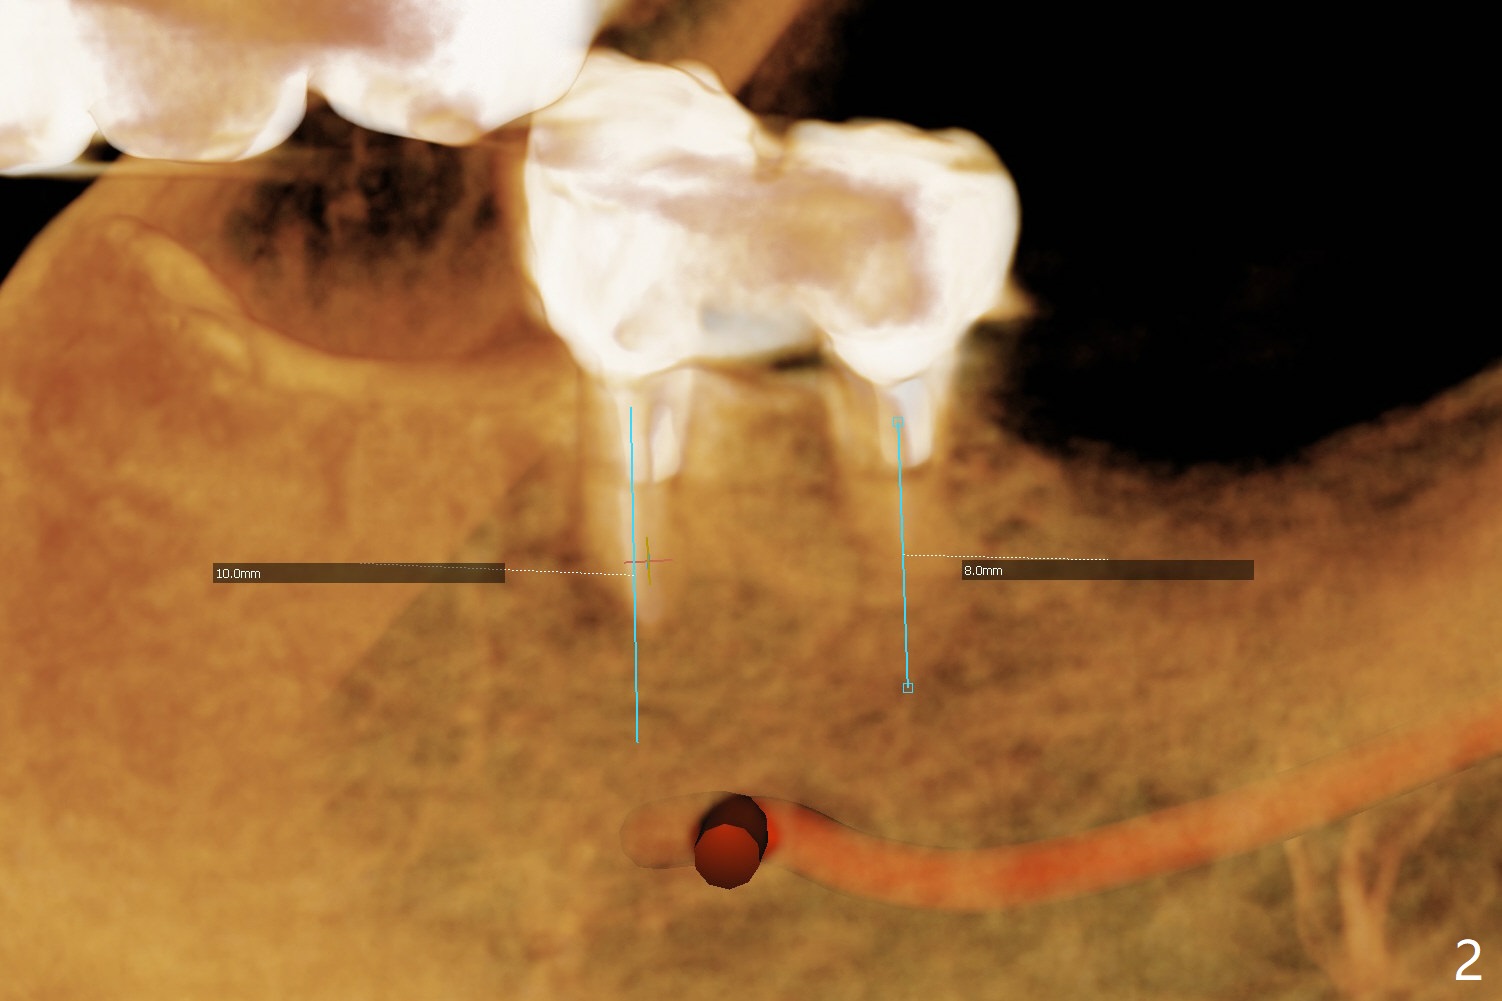

When the patient returns 4 months post #26 implant 2nd placement, the fractured crowns at #20 and 21 are loose. The roots are not difficult to remove. Since the bone height is limited (Fig.1,2), immediate implants are 3.8x8 and 3.8x10 mm, respectively with insertion torque >30 Ncm. Ball abutments (3.9x2 mm) are placed at #20 and 21; the existing lower RPD is soft relined using #26 1-piecee implant as an abutment. The retention of the RPD improves. Another implant will be placed in the lower right quadrant. One month 10 days postop, the ball abutment at #21 seems to be low (Fig.6). It is removed after laser gingivectomy and replaced with a ball abutment with 4 mm cuff. When the patient closes without RPDs, the 1-piece implant at #26 is barely buccal to the upper ridge (Fig.7). It appears that crowns have to be fabricated at #20,21,26 and 27 prior to refabrication of the lower RPD.